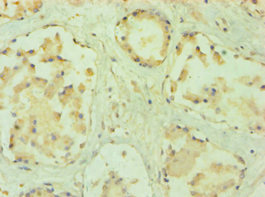

• Immunohistochemistry of paraffin-embedded human prostate tissue using CSB-PA018574ESR2HU at dilution of 1:100

• Immunohistochemistry of paraffin-embedded human placenta tissue using CSB-PA018574ESR2HU at dilution of 1:100